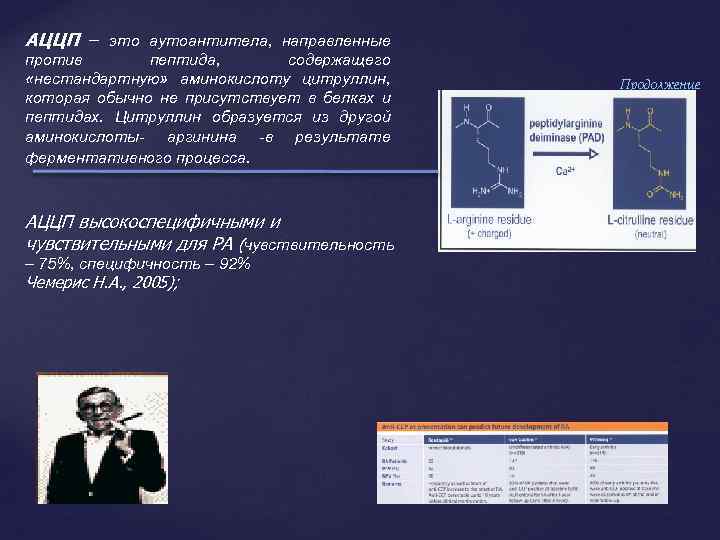

АЦЦП – это аутоантитела, направленные против пептида, содержащего «нестандартную» аминокислоту цитруллин, которая обычно не присутствует в белках и пептидах. Цитруллин образуется из другой аминокислоты- аргинина -в результате ферментативного процесса. АЦЦП высокоспецифичными и чувствительными для РА (чувствительность – 75%, специфичность – 92% Чемерис Н. А. , 2005); Продолжение

АЦЦП – это аутоантитела, направленные против пептида, содержащего «нестандартную» аминокислоту цитруллин, которая обычно не присутствует в белках и пептидах. Цитруллин образуется из другой аминокислоты- аргинина -в результате ферментативного процесса. АЦЦП высокоспецифичными и чувствительными для РА (чувствительность – 75%, специфичность – 92% Чемерис Н. А. , 2005); Продолжение